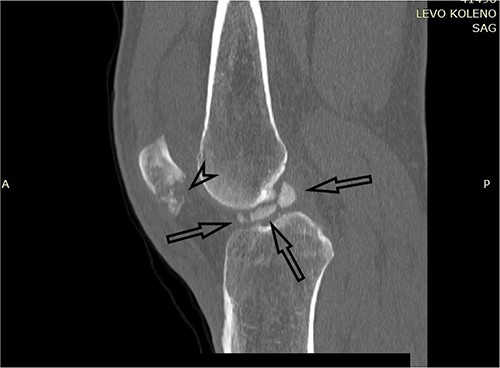

A plain X-ray of the left knee revealed a single defect of the lateral femoral condyle in the anteroposterior (AP) view. The lateral view showed a free bone fragment with a defect (Fig. 1A and B). Additional diagnostic imaging was performed. A computerized tomography (CT) scan revealed multifragmentary (three fragments) fracture of the lateral femoral condyle accompanied by a fracture of the left patella (Fig. 2). The fracture was classified as 33B3.2 according to the Association for Osteosynthesis–Orthopaedic Trauma Association (AO/OTA), Type II C (according to Letenneur) [2]. It was decided that single-approach surgery (posterior or anterior) would be insufficient for acceptable anatomic reduction and proper fixation of all the fragments because of the fracture complexity. The preoperative plan consisted of a posterior-first approach (extended posterior approach to the proximal tibia) for fixation of the largest (posterior) fragment (Fig. 3) followed by an arthroscopic anterior approach (for anterior fragment fixation). The predetermined time interval between the two procedures was to allow the healing of the joint capsule after the index surgery. Operative fixation of the patellar fracture was not indicated.

CT scan of the left knee (sagittal) focusing on the largest posterior fragment (arrow).